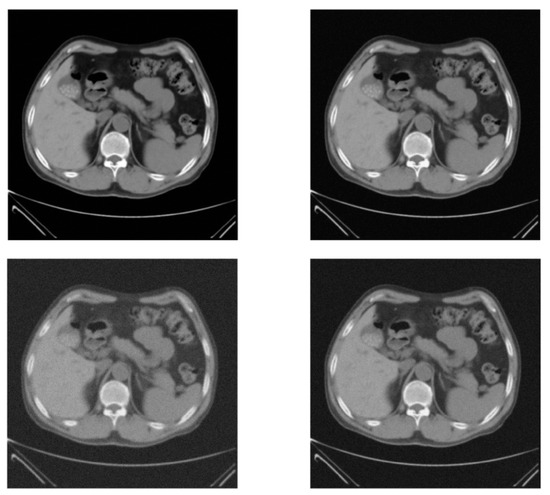

| Figure 4 | SART | ----- | 42.4213 ± 0.2456 | 44.1773 ± 0.2312 | 45.1659 ± 0.3241 |

| SART + TV | ----- | 43.8746 ± 0.2891 | 45.4988 ± 0.2561 | 46.6102 ± 0.2134 | |

| Wavelet | ----- | 45.8239 ± 0.2211 | 46.2769 ± 0.2341 | 48.4986 ± 0.2781 | |

| Proposed approach | 45.2660 ± 0.1561 | 47.3095 ± 0.1861 | 48.3834 ± 0.1734 | 49.6093 ± 0.1709 | |

| Figure 4 | SART | ----- | 0.9491 ± 0.0026 | 0.9707 ± 0.0034 | 0.9795 ± 0.0045 |

| SART + TV | ----- | 0.9553 ± 0.0045 | 0.9774 ± 0.0034 | 0.9833 ± 0.0044 | |

| Wavelet | ----- | 0.96 07 ± 0.0022 | 0.9812 ± 0.023 | 0.9901 ± 0.0024 | |

| Proposed approach | 0.9643 ± 0.0023 | 0.9730 ± 0.0021 | 0.9879 ± 0.0032 | 0.9952 ± 0.0027 | |